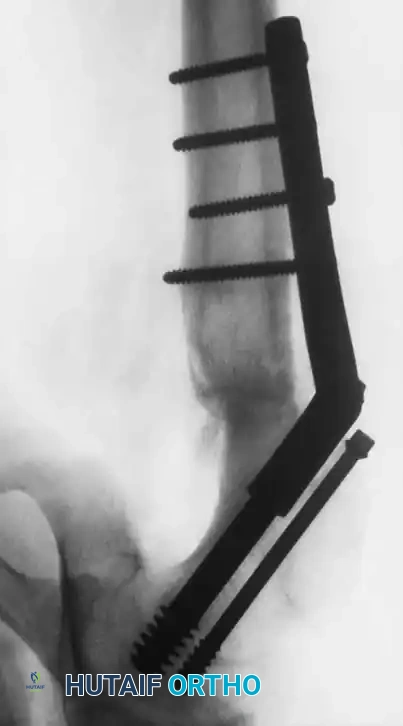

Fig. 33-129 Principle of dynamic screw fixation. A short screw thread (10 mm) engages the epiphysis only, and the screw and washer are left protruding 15 to 20 mm to accommodate continued growth.

Using a 7 mm cannulated screw with 10-mm threads placed precisely in the center of the femoral head, the screw is left protruding 15 to 20 mm laterally. In their study of 29 hips, the femoral neck continued to grow approximately 15 mm without premature physeal closure or loss of fixation.